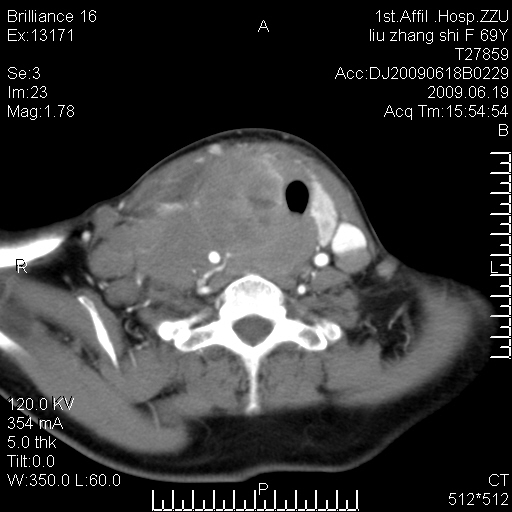

标题: CT26782:女,69岁,颈部占位,3天后公布病理结果。

【病理证实系列】女,69岁,颈部占位,有病理结果,3天后公布。(由于病例时间较久,临床资料不全,请网友见谅)本系列将有几百种常见、少见及罕见病例,均经病理证实。病例资料来自郑州大学第一附属医院。与网友共享,本人有空就发。

甲状腺癌并颈部淋巴结转移。感谢楼主的良苦用心,谢谢。

甲状腺癌并颈部淋巴结转移。

需与鼻咽癌鉴别!

支持甲状腺癌广泛侵及周围结构并颈部淋巴结转移。

鉴别:淋巴瘤、恶性神经源性病变、恶性纤维组织细胞瘤。

病理结果:颈部非霍奇金淋巴瘤。